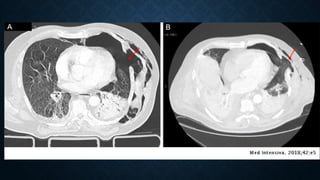

Tension haemopneumothorax. Axial contrast-

enhanced CT at mediastinal window shows a

right tension haemopneumothorax with

heterogeneous increased density due to

presence of blood clots and a significant shift

of the mediastinum contralaterally.

Tension pneumothorax. Sagittal reformatted CT image

at lung window showing tension pneumothorax with

significantly collapsed lung at the posterior part of the

hemithorax associated with ipsilateral pleural effusion.